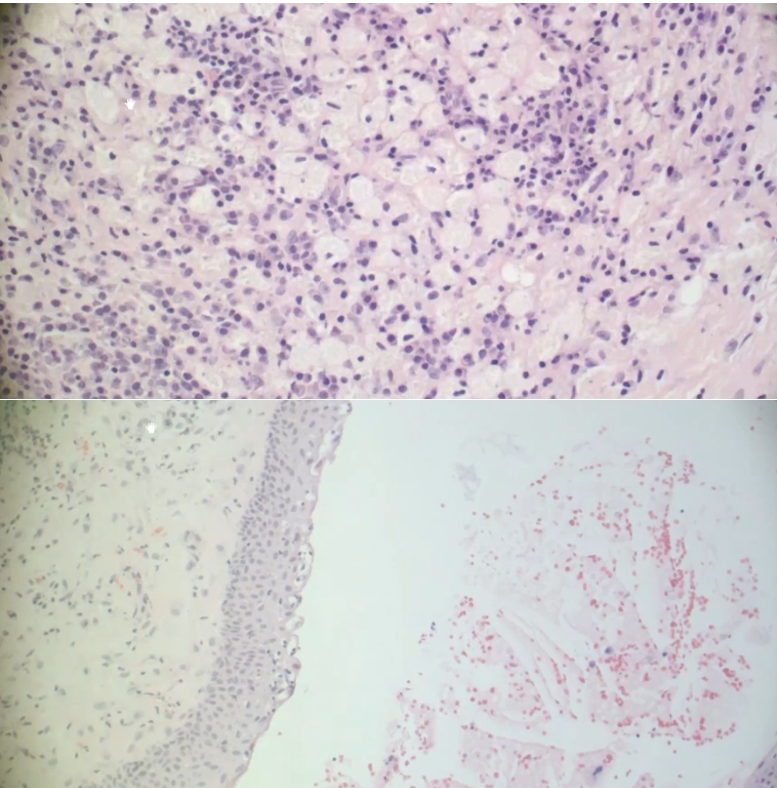

What does the histology look like for a periapical granuloma?

A

• connective tissue with many types of inflammatory cells

• macrophages

• plasma cells

• neutrophils

• lymphocyte

• DO NOT SEE EPITHELIUM

What does the histology look like for a periapical cyst?

• Epithelium!!

• some neutrophils

What is the main difference between a periapical abcess, granuloma, and cyst?

abscess - mostly neutrophils

granuloma - NO epthelium and mix of inflammatory cells

cyst - epithelium and mix of inflammatory cells